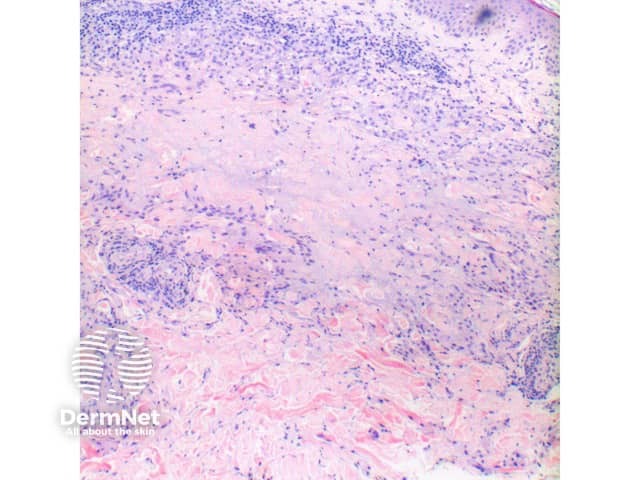

Figure 2